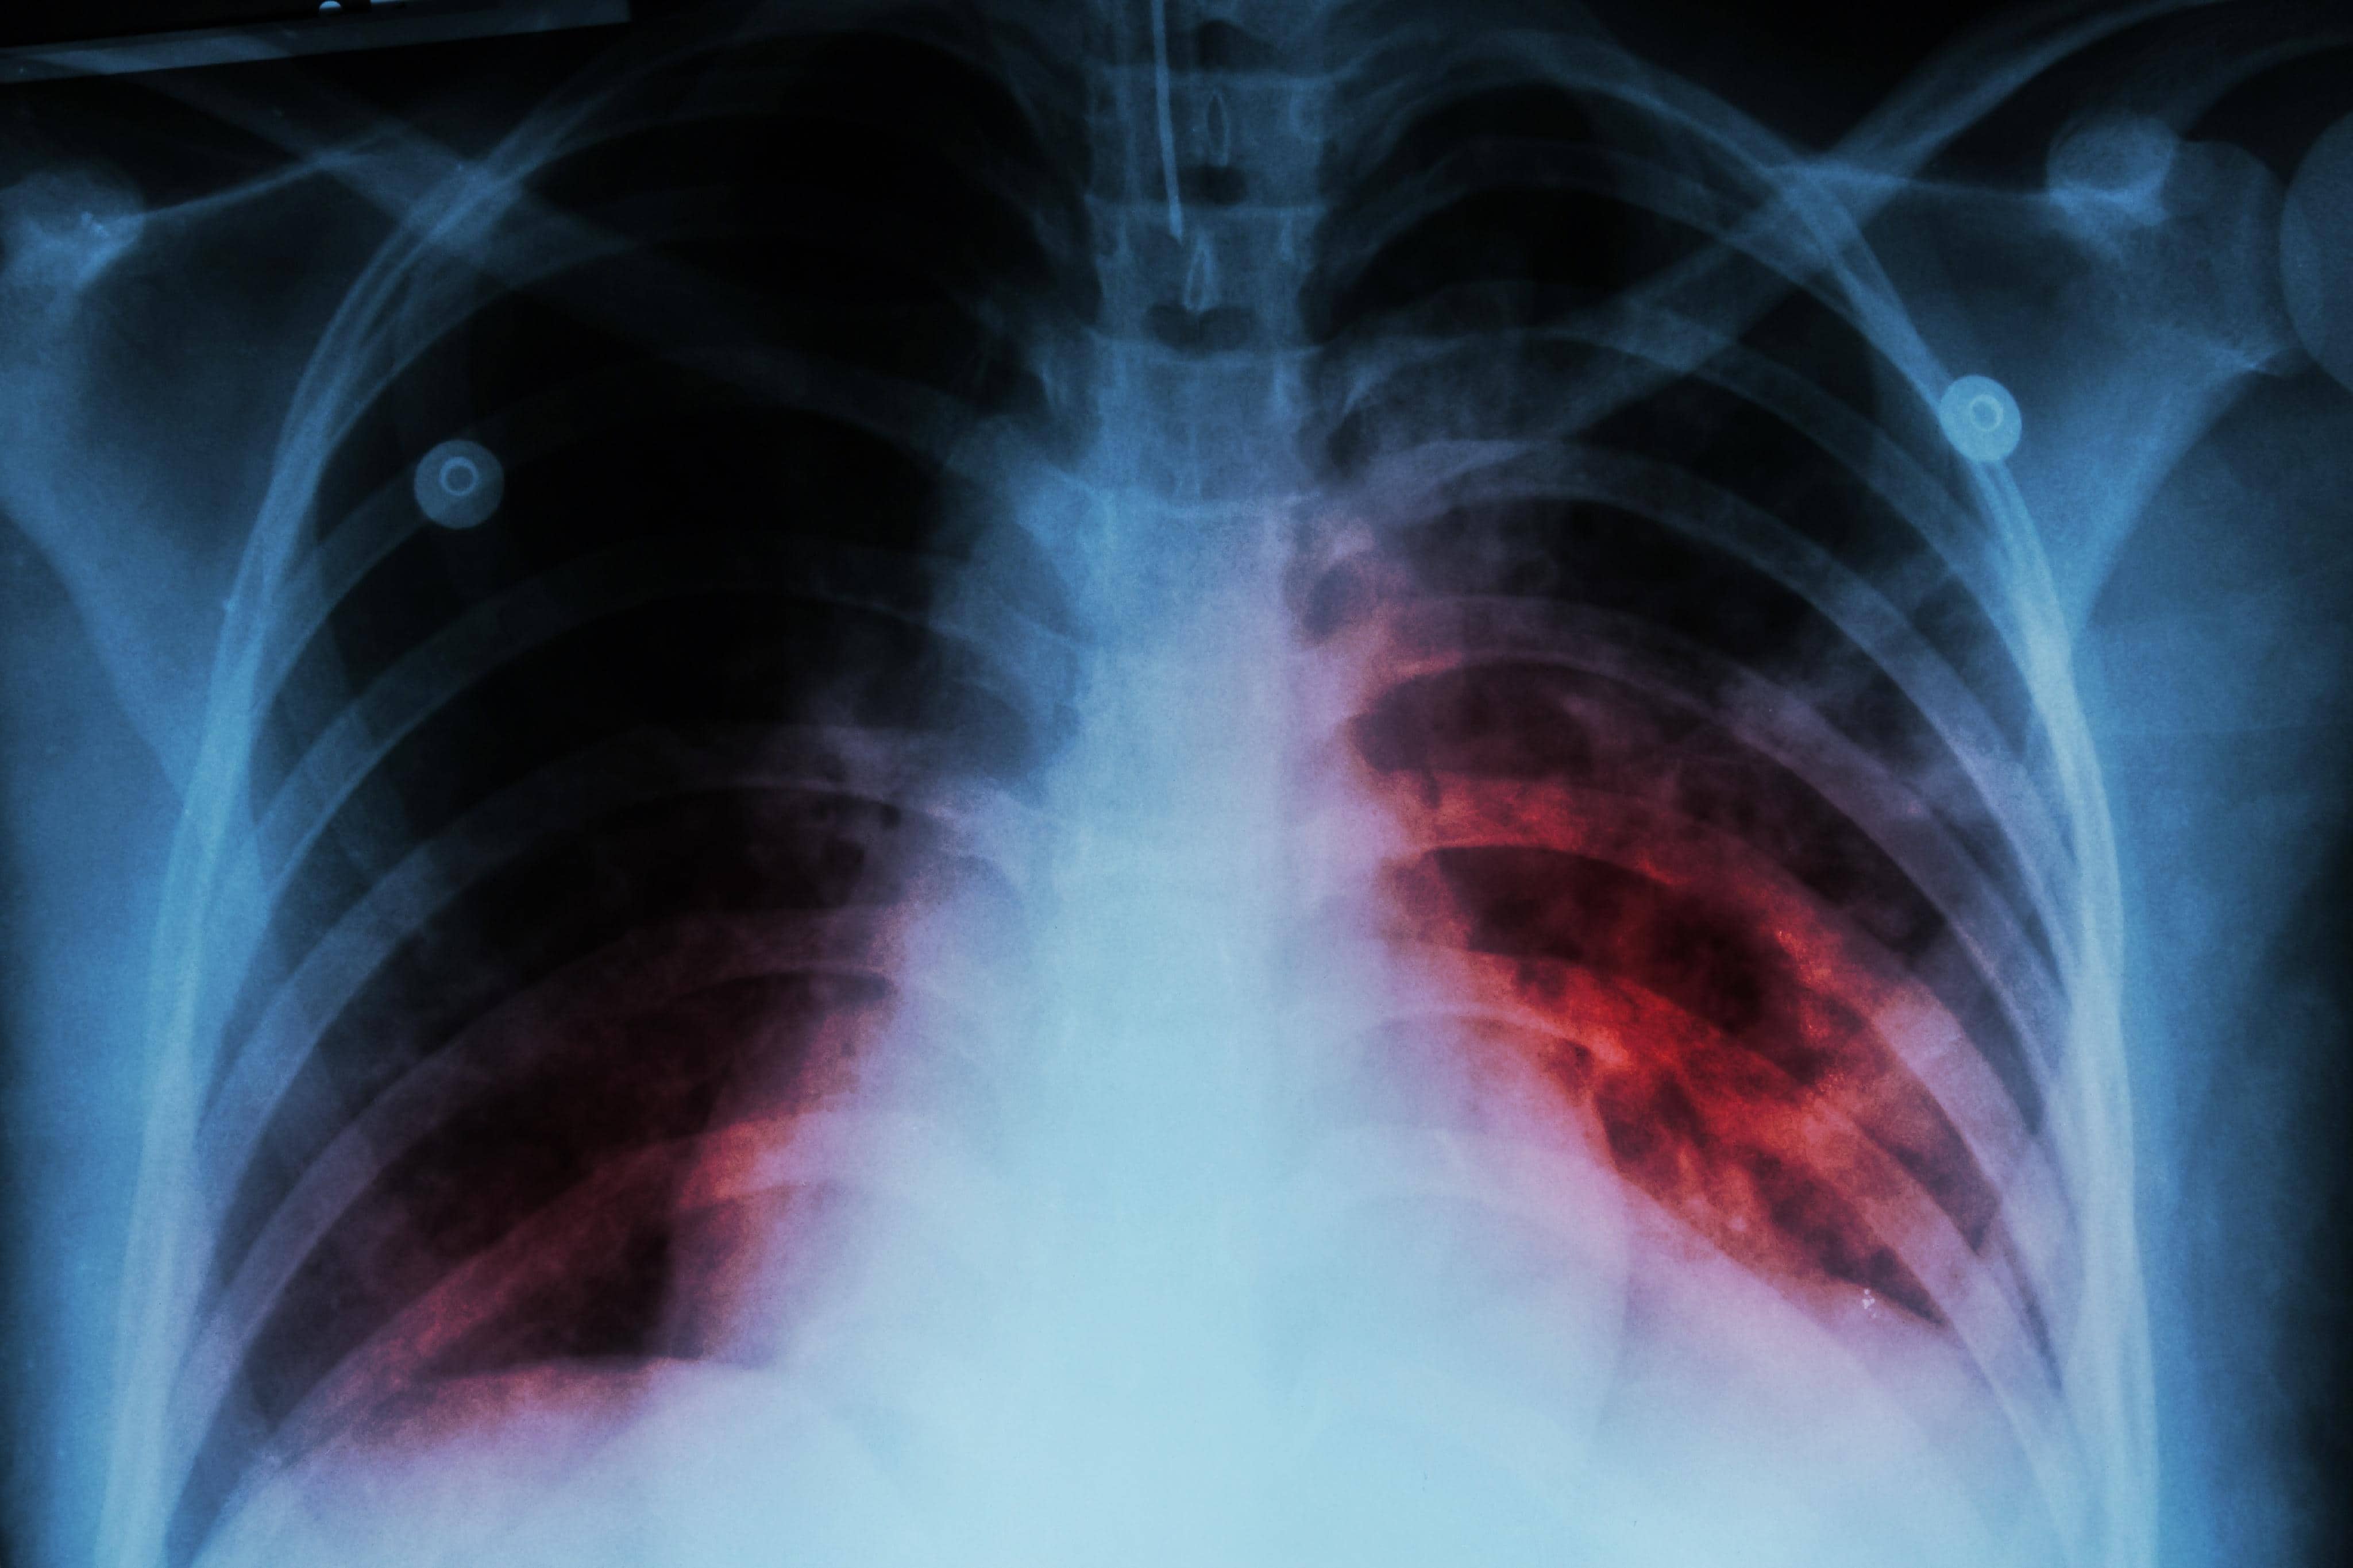

Incrementan casos de tuberculosis binacional en la frontera de Coahuila

Piedras Negras, Coahuila.— El programa binacional de tuberculosis en la franja fronteriza reportó un incremento en los casos registrados durante 2026, con especial atención en pacientes con vínculos entre México y Estados Unidos.